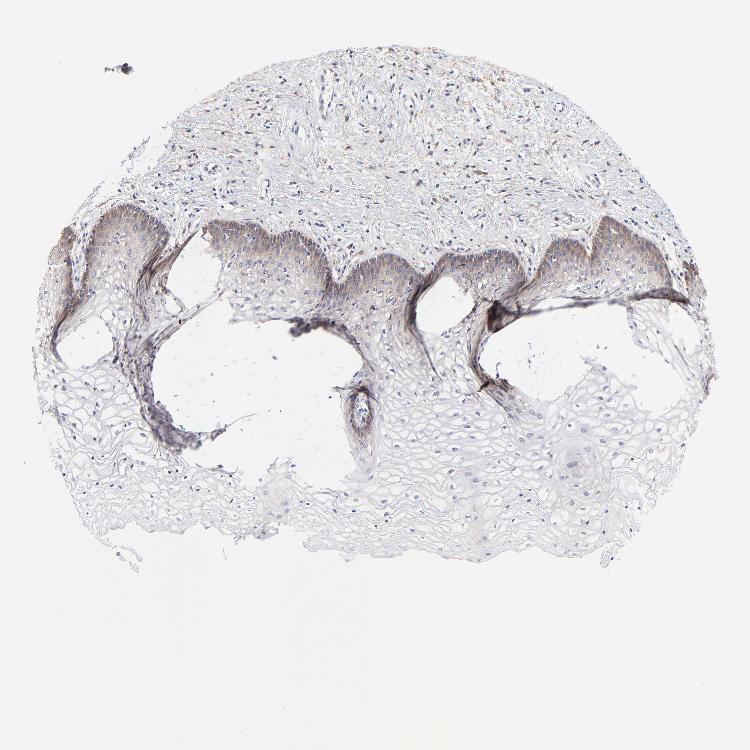

VAGINA - Antibody stainingi

Antibody staining in the annotated cell types in the current human tissue is reported as not detected, low, medium, or high, based on conventional immunohistochemistry profiling in selected tissues. This score is based on the combination of the staining intensity and fraction of stained cells.

Each image is clickable and will lead to virtual microscopy that enables deeper exploration of all samples and also displays staining intensity scores, fraction scores and subcellular localization as well as patient and tissue information for each sample.

Antibody HPA003222

Squamous epithelial cells Low